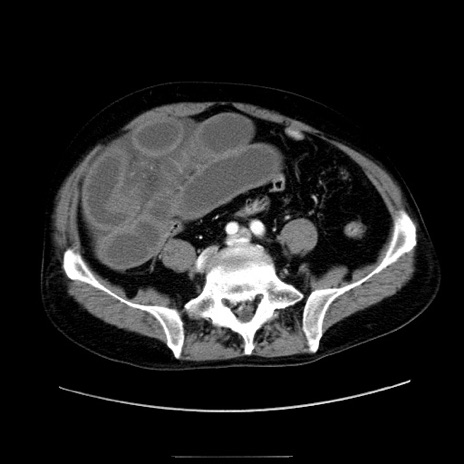

症例30(横断像)

【症例】80歳代男性

【主訴】臍周囲痛

【現病歴】約6時間前から臍下部痛が出現。次第に腹部膨隆・背部痛も生じてきたため来院。背部痛の場所は変化しない。

【身体所見】意識清明、BT 36.3℃、BP  131/87mmHg、P 87bpm、SpO2 100%(RA)、臍周囲自発痛・圧痛あり、反跳痛なし、自発痛部位に一致して板状硬あり、腹部膨隆、腸雑音減弱、CVA tenderness両側陰性。

【データ】WBC 19600、CRP 0.33